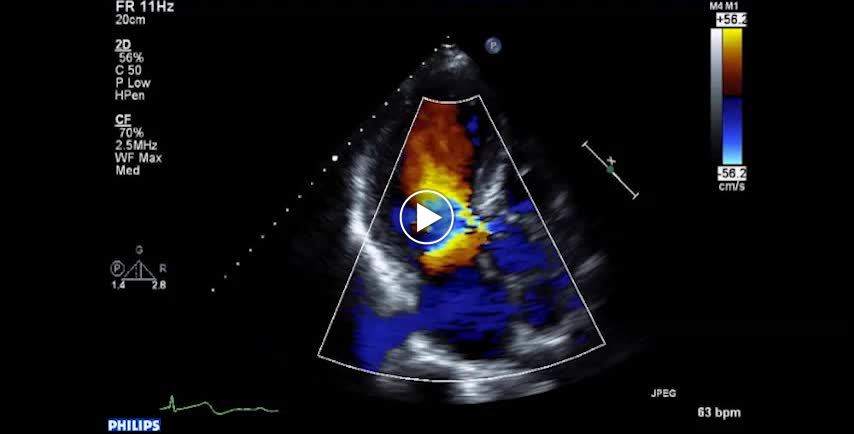

• 図8 MR+ARの組み合わせによる往復雑音 a

• 図8 MR+ARの組み合わせによる往復雑音 b